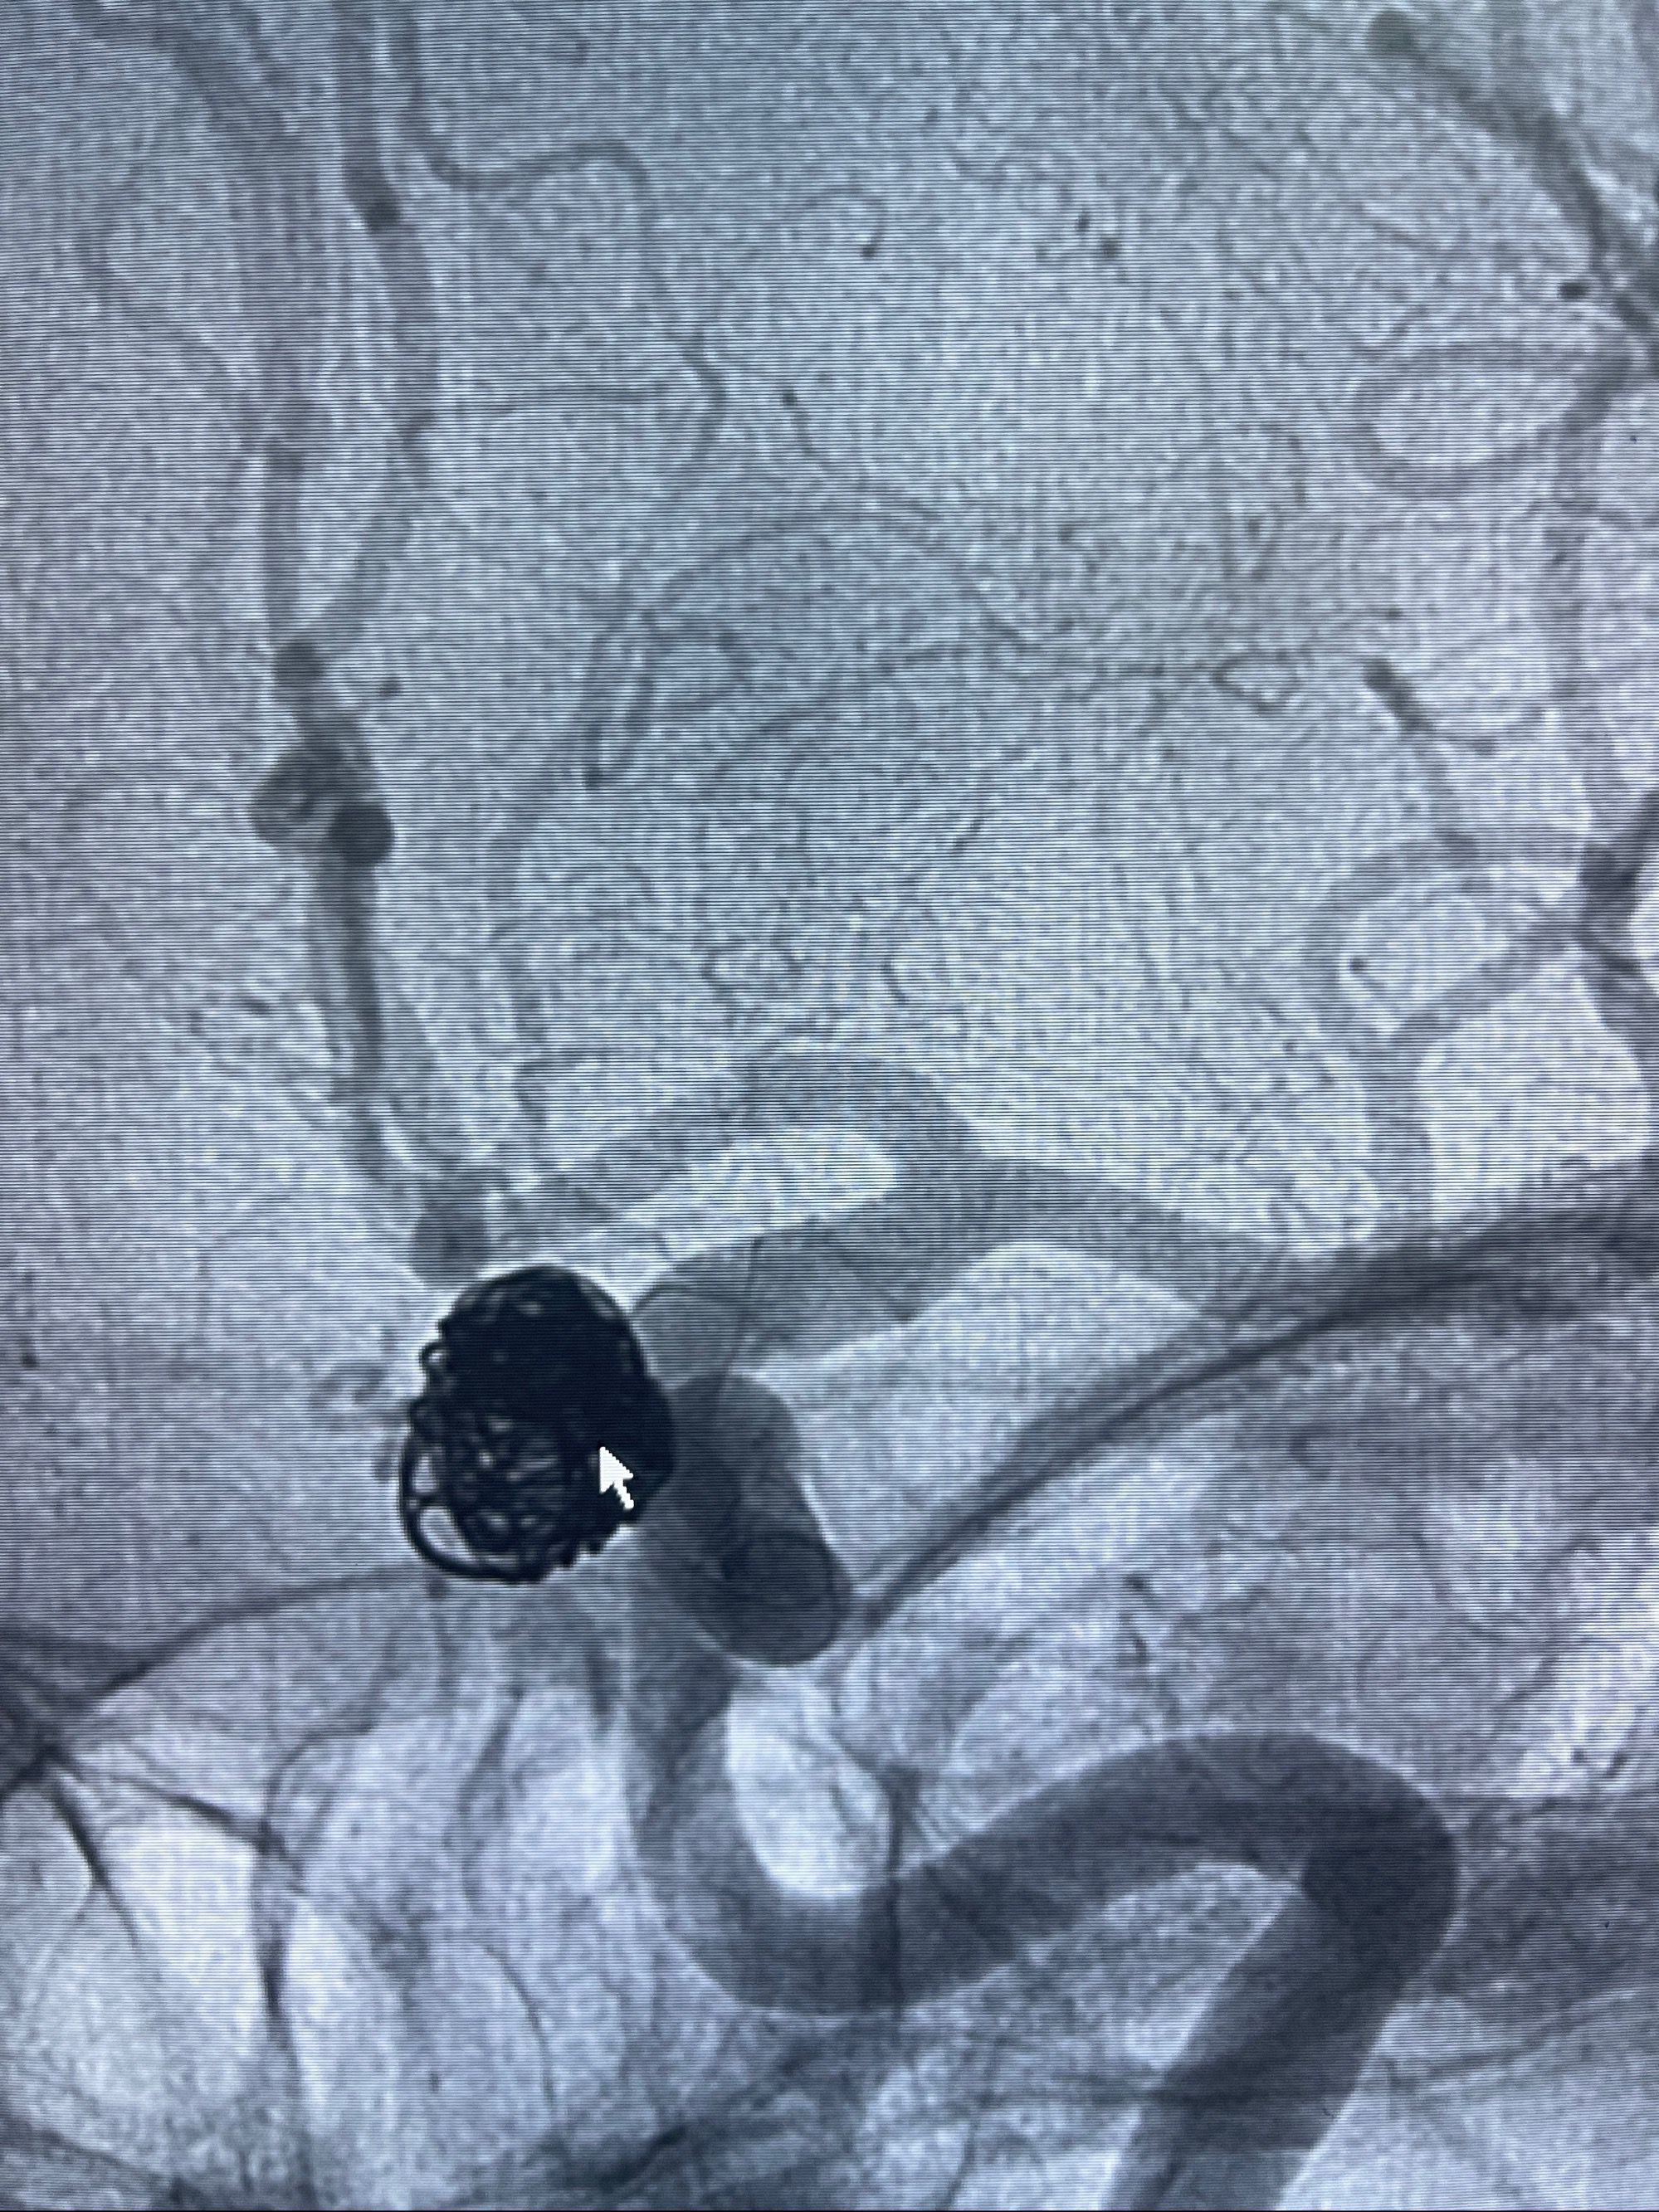

密网支架辅助栓塞

- 加奇微弹簧圈:7*30/6*20/5*20/2*8

术后3D显示支架贴壁佳